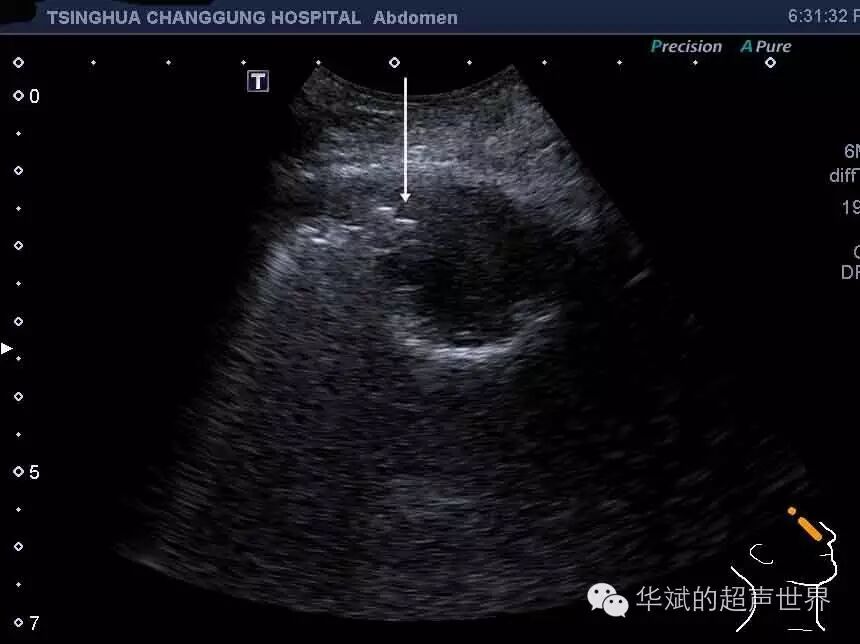

典型病例1 患者女,40岁,上感两周,右侧头痛及颌面部疼痛一周,黄脓涕,超声示右侧上颌窦积液

图3 急性上颌窦炎。右图为正常的左侧上颌窦声像图,窦腔内结构不能显示。左图为右侧大致呈三角形的上颌窦内积液,可以清晰显示上颌窦的侧壁和后壁(箭头)。

图4急性上颌窦炎。纵断扫查显示上颌窦内的气体和液体交界处(长箭头)。这一断面可以大致估计窦腔内的积液量的多少。